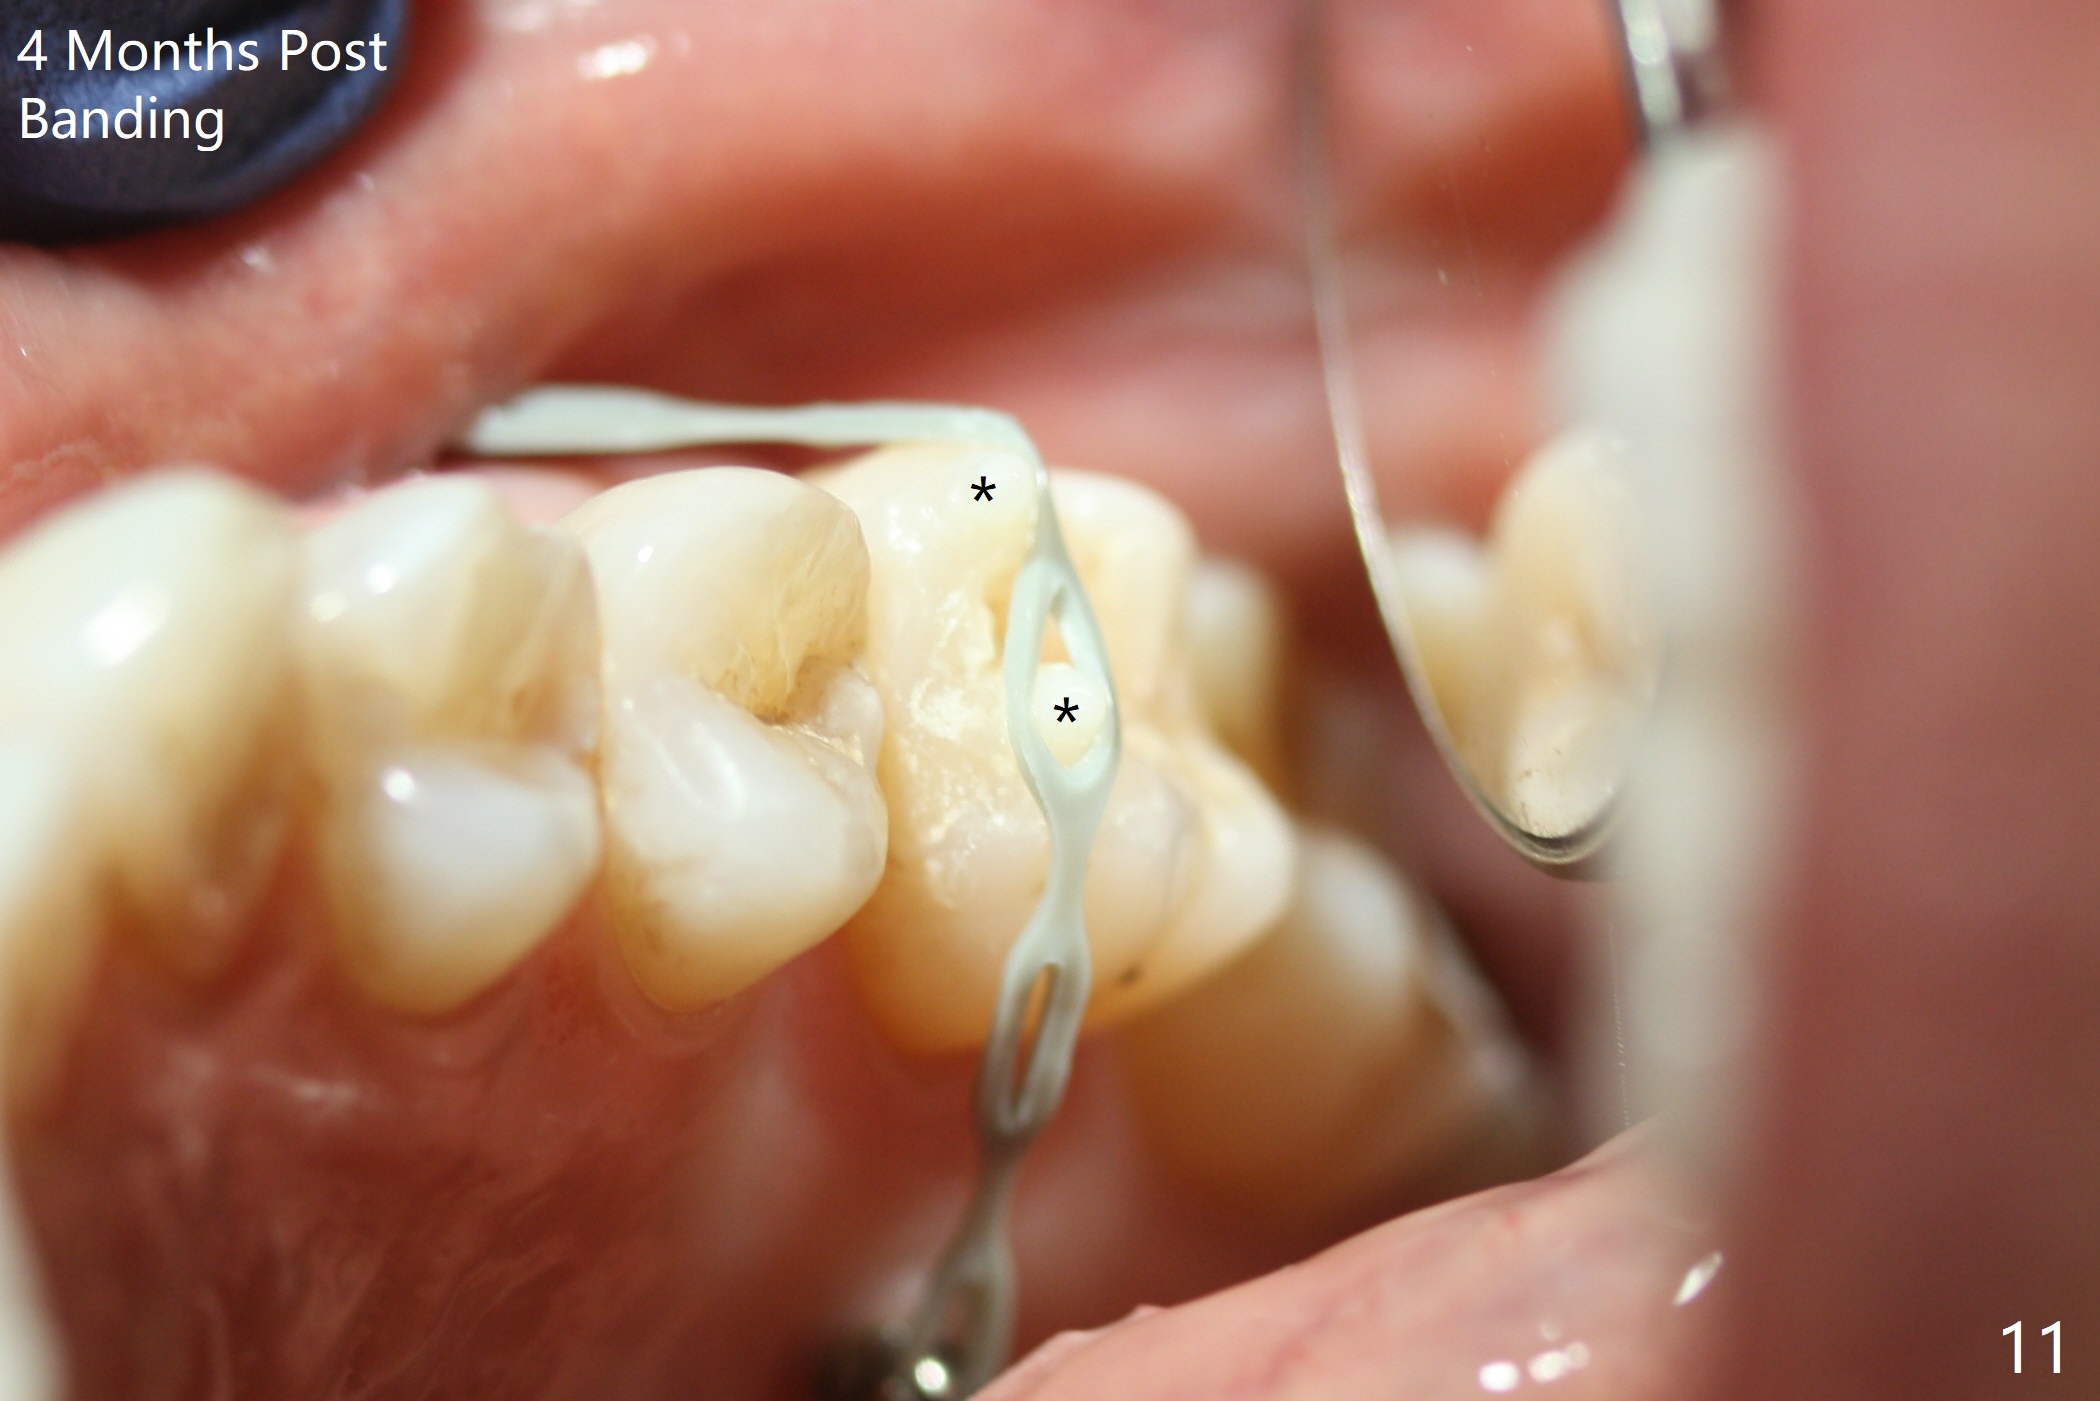

It looks as if the tooth #3 is blocked by the neighboring teeth. The proximal surfaces are reduced 1.5 months post orthodontic intrusion. Fourteen days later, the gap exists distal (Fig.10 *). It appears that the power chains placed on the natural groove of the tooth (white line) mesializes the tooth. Then the power chains are placed mesial to the mesiopalatal cusp by placing 2 of composite (Fig.11); one month later, the distal gap closes (Fig.12). The patient feels less pressure against the teeth anterior to the tooth #14. At the same time, the latter appears to have been intruded. The tooth appears to have been intruded radiographically 4 months post retraction (Fig.13).